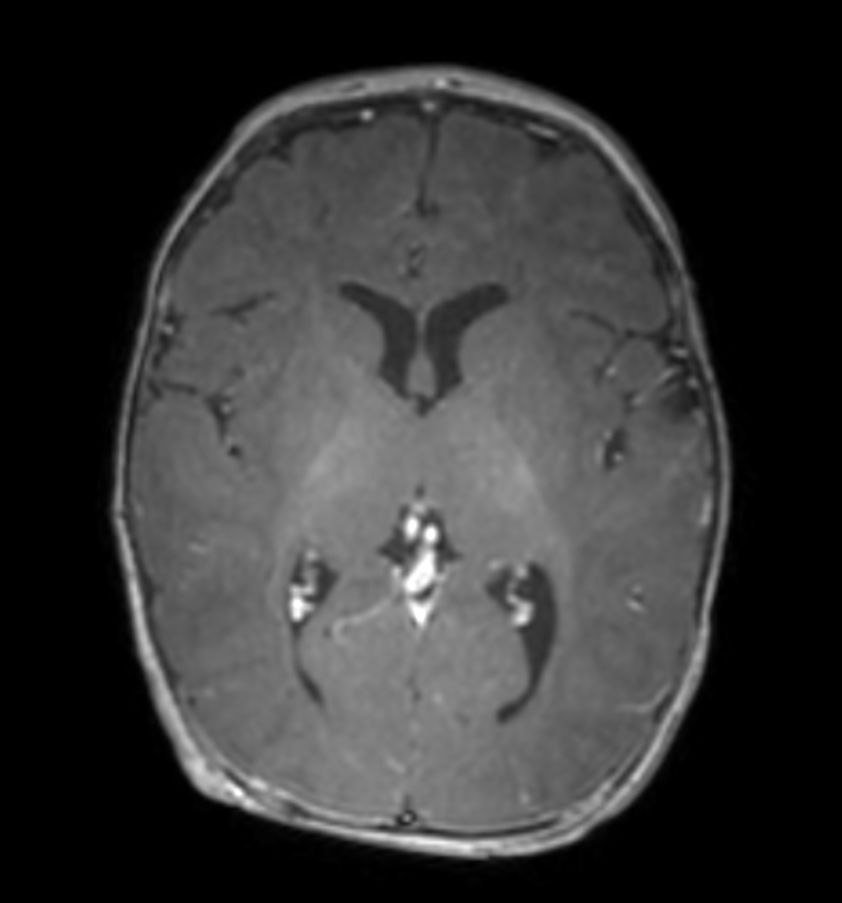

3D T1w TFE with ComforTone -  Axial reformat